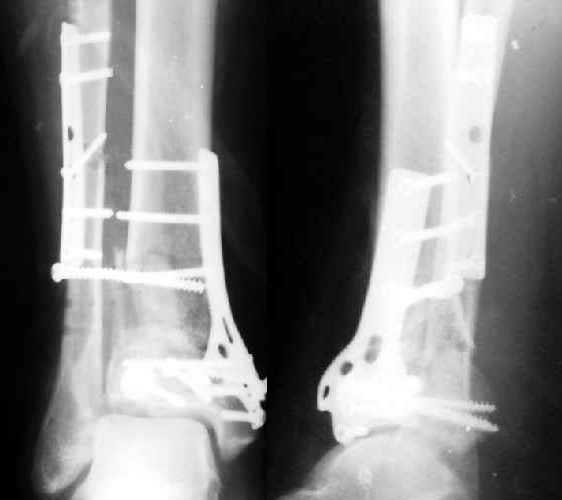

Итог операцииЧерез 1,5 месяца

Полтора месяца назад мужчине 45 лет выполнена открытая репозиция дистального отдела большеберцовой кости и внутренняя фиксация (снимок 1).

На другой ноге - переломы нескольких плюсневых костей. Из-за сопутствующих урологических проблем через две недели перевели в другое учреждение, там был вынужден ходить с костылями с нагрузкой на обе ноги.При контрольной явке к нам через месяц обнаружилась несостоятельность фиксации (снимок 2). Какие выходы их положения можно тут предложить?